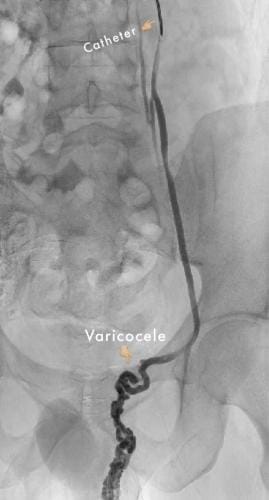

Varicocele can be treated by an embolization procedure or surgery. Embolization is a non-surgical, outpatient, minimally invasive technique that uses x-ray guidance to place tiny coils and embolic fluid in the abnormal blood vessels causing them to close down.

After a local anesthetic, a tiny catheter is placed into a vein in the groin or neck. The Interventional Radiologist then uses the x-ray equipment to guide the catheter into the variococele. A combination of metallic coils and a special fluid are placed directly into the abnormal veins causing them to close. Once the veins are blocked, the catheter is removed.